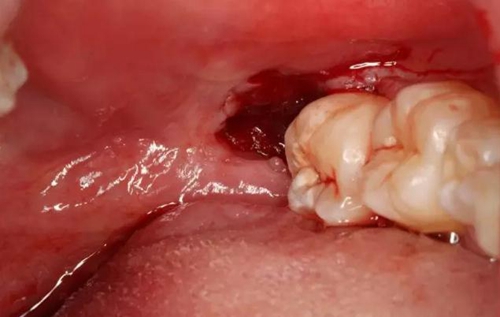

圖4.38頰側(cè)牙齦腫脹、探診出血